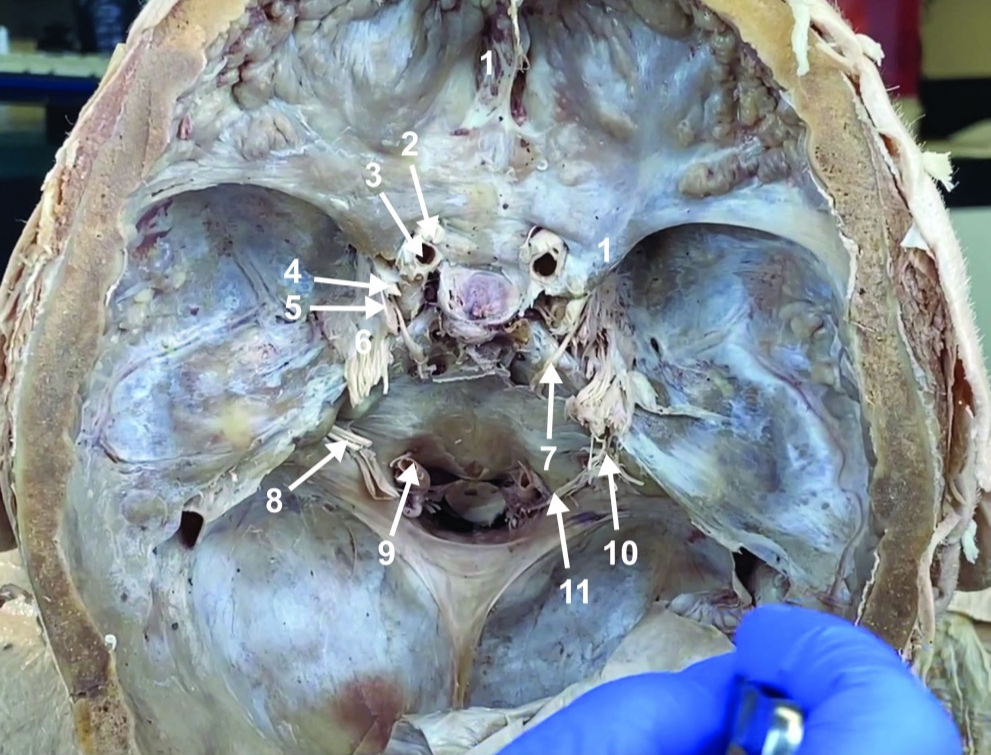

Foramen magnum

Foramen ovale

Foramen spinosum

Cribiform plate

Optic n. (CN II)

Internal carotid a. (ICA)

Occulomotor n. (CN III)

Trochlear n. (CN IV)

Trigeminal n. (CN V)

Abducent n. (CN VI)

Facial and vestibulocochlear n. (CN VII and VIII)

Vertebral a.

Glossopharyngeal and vagus n. (CN IX and X)

Root of spinal accessory n. (root of CN XI)

Ophthalmic division of CN V (CN V1)

Maxillary division of CN V (CN V2)

Mandibular division of CN V (CN V3)

Foramen rotundum

Foramen ovale

Trochlear n. (CN IV)

Abducent n. (CN VI)